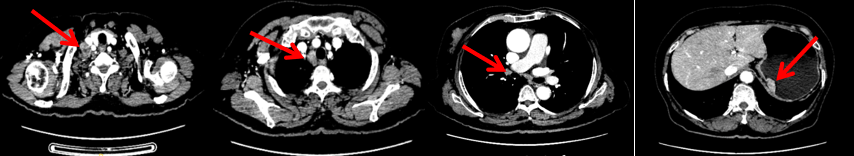

颈胸腹盆腔CT

右乳外上象限占位,考虑乳腺癌;右侧锁骨上、上纵隔及右肺门多发淋巴结转移(较大者24*15mm)。胃贲门处小弯侧胃壁明显增厚(26*12mm),考虑胃癌可能,周围脂肪间隙清;颈部未见明确异常。头颅MR未见脑转移。

2023.6.26复查PET-CT

1.右乳外上象限乳腺癌病灶(22*16mm),对比2023-04-14 CT(26*24mm)较前缩小,FDG代谢活跃。右侧腋窝小淋巴结(5mm),较前稍缩小,代谢不活跃。右侧锁骨上区、上纵隔淋巴结转移瘤(24*18mm),现大小同前相仿,代谢活跃(SUV:6.7)。

2.现胃贲门部术后改变,术区未见明显异常活性灶。

3.左乳、左侧胶窝术后改变,未见明显异常活性灶。双肺小结节。考虑炎性结节可能,建议复查;双肺门及纵隔另反应性淋巴结。

2024-11-5复查CT:右乳外上象限占位(11mm×9mm),较前明显缩小;上纵隔及右肺门多发淋巴结转移缩小;右锁骨上区淋巴结较前增大。余部位未见肿瘤转移及复发征象。